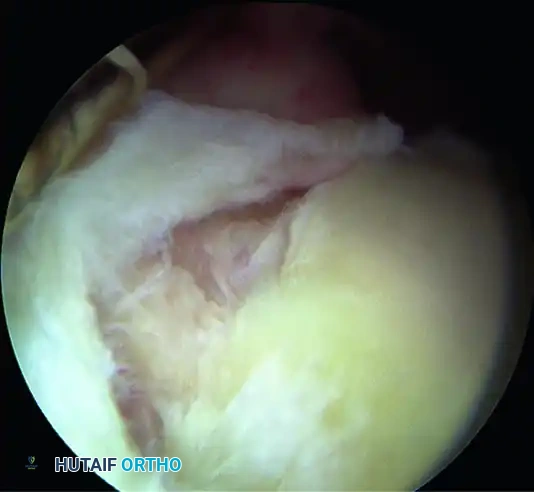

Type II SLAP Lesion

• Pathology: The most common SLAP variant. Involves a pathological detachment of both the superior labrum and the biceps anchor from the superior glenoid rim. These lesions frequently progress posterior to the biceps anchor.

Image

• Biomechanics & Diagnosis: Pagnani et al. demonstrated that Type II lesions cause a significant increase in anteroposterior and superoinferior glenohumeral translation in laboratory settings. Clinically, while they may not produce overt gross instability, they result in profound "microinstability" symptoms. The diagnosis is confirmed intraoperatively via the Peel-Back Test: The arm is removed from traction and placed in 90 degrees of abduction. As the shoulder is externally rotated to 90 degrees, the detached labrum is observed displacing medially over the scapular neck.

• Treatment Algorithm: Type II lesions must be addressed to prevent further destabilization.

• Patients < 35 Years Old: Arthroscopic repair using suture anchors and knot-tying (or knotless) techniques is the gold standard. Kim et al. reported 94% satisfactory results in this demographic.

• Patients > 50 Years Old: Older patients exhibit diminished healing potential, a higher risk of postoperative stiffness, and persistent pain following repair. In this demographic, biceps tenodesis (with or without labral debridement) yields vastly superior and more predictable clinical outcomes.